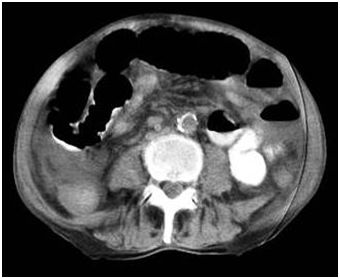

65-year-old man was admitted to our emergency department with nausea, vomiting, distension and colicky abdominal pain of 5days' duration. He had regulated hypertension and chronic obstructive pulmonary disease for fifteen years. He had undergone gastric and biliary surgery 25years ago. Physical examination revealed distension and tender abdomen with few poor bowel sounds especially in right mid-lower abdomen. Laboratory tests showed leukocytosis. Plain abdominal X-ray demonstrated the presence of a round hyperdense mass with calcified margins in the right lower quadrant as well as enlarged loops of small bowel (Figure 1) CT scan of the abdomen showed pneumobilia, a calcified mass impacted in the terminal ileum (Figure 2).

Figure 2 CT scan revealed the opacity in intestinal lumen.

The clinical symptoms occasionally include nausea, vomiting, pain and hematemesis. Laboratory findings may demostrate impaired liver functions with high bilirubin and alkaline phosphophatase levels etc. The diagnosis is really a challenge for surgeon and usually depends on the radiographic findings. Preoperative conventional diagnostic tools generally do not demonstrate bilioenteric fistula and delay in diagnosis would be inevitable resulting higher morbidity and mortality rates. Whereas radiologic findings of mechanical bowel obstruction can easly be visualized in plane abdominal radiograms and computed tomography, pneumobilia would not be demonstrated in most cases.2,6,9 The classic Rigler’s triad of radiography includes mechanical bowel obstruction, pneumobilia, and an ectopic gallstone within bowel lumen.10 In our case, abdominal CT scan and plain radiograph also demonstrated dilated intestinal segments with stone opacity and gas in the biliary tree.